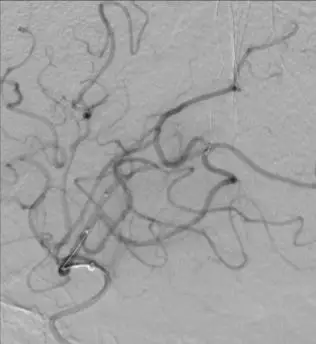

颈内动脉DSA提示颈内动脉狭窄,远端血流较差。 颈内动脉置入9mm-40mm Protege支架,收回保护伞后DSA提示血管再通良好,给予替罗非班7ml/h。 术后即刻查体NIHSS评分8分,给予替罗非班10ml/h泵入,持续24h。 术后第2天复查灌注成像提示双侧半球基本对称,CTA提示右侧颈内动脉以及大脑中动脉通畅。

术后结论 右侧颈内动脉C1段闭塞合并右侧MCA上干闭塞,M2远端分支闭塞以及MCA下干起始段局部血栓形成。 术后随访 术后3月mRS评分:1分。